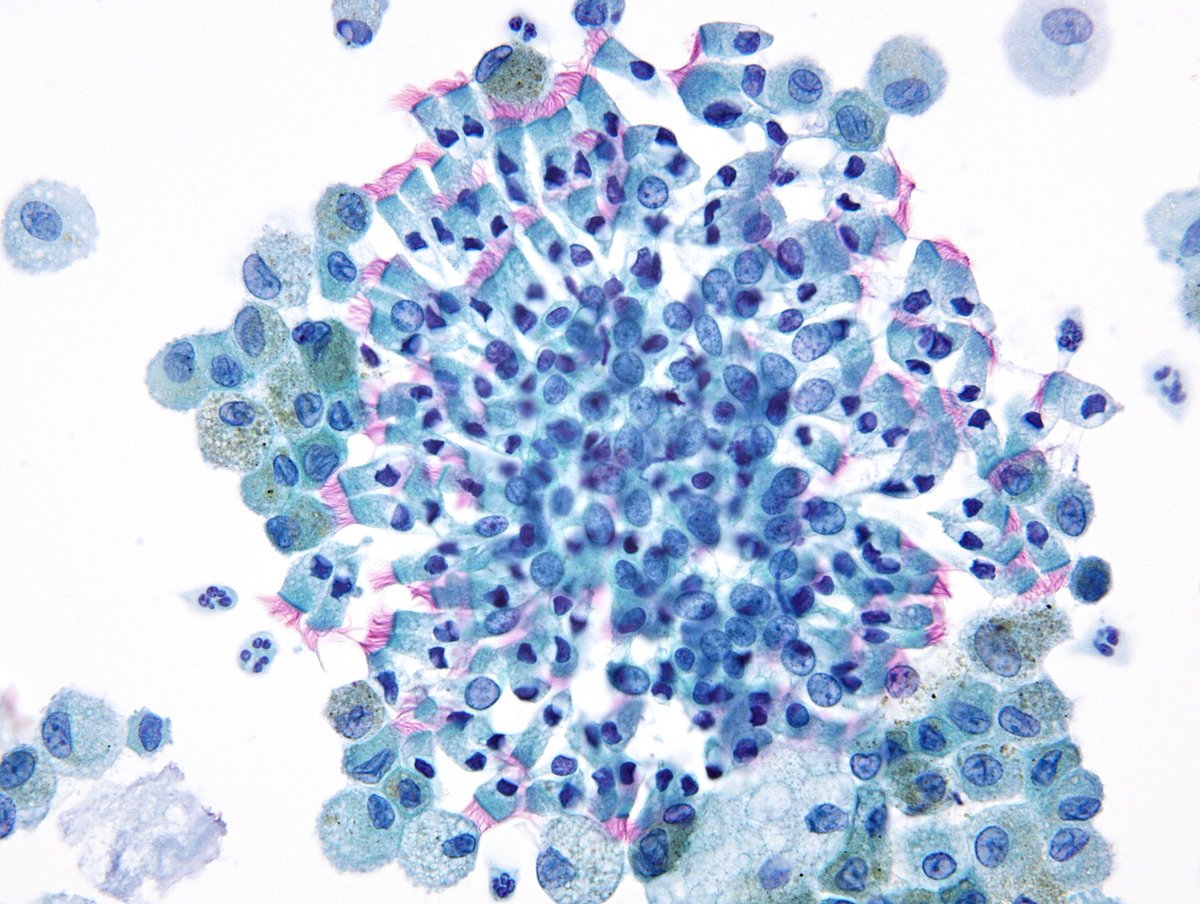

A teaching point from our Editors. How do you distinguish between intrapancreatic bile duct carcinoma and pancreatic ductal carcinoma? Samuel Freire